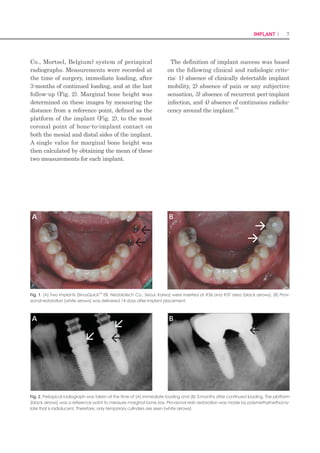

Co., Mortsel, Belgium) system of periapical

radiographs. Measurements were recorded at

the time of surgery, immediate loading, after

3-months of continued loading, and at the last

follow-up (Fig. 2). Marginal bone height was

determined on these images by measuring the

distance from a reference point, defined as the

platform of the implant (Fig. 2), to the most

coronal point of bone-to-implant contact on

both the mesial and distal sides of the implant.

A single value for marginal bone height was

then calculated by obtaining the mean of these

two measurements for each implant.

Fig. 2. Periapical radiograph was taken at the time of (A) immediate loading and (B) 3-months after continued loading. The platform

(black arrows) was a reference point to measure marginal bone loss. Provsional resin restoration was made by polymethylmethacry-

late that is radiolucent. Therefore, only temporary cylinders are seen (white arrows).

Fig. 1. (A) Two implants (SinusQuickTM

EB, Neobiotech Co., Seoul, Korea) were inserted at #36 and #37 area (black arrows). (B) Prov-

sional restoration (white arrows) was delivered 14 days after implant placement.

A B